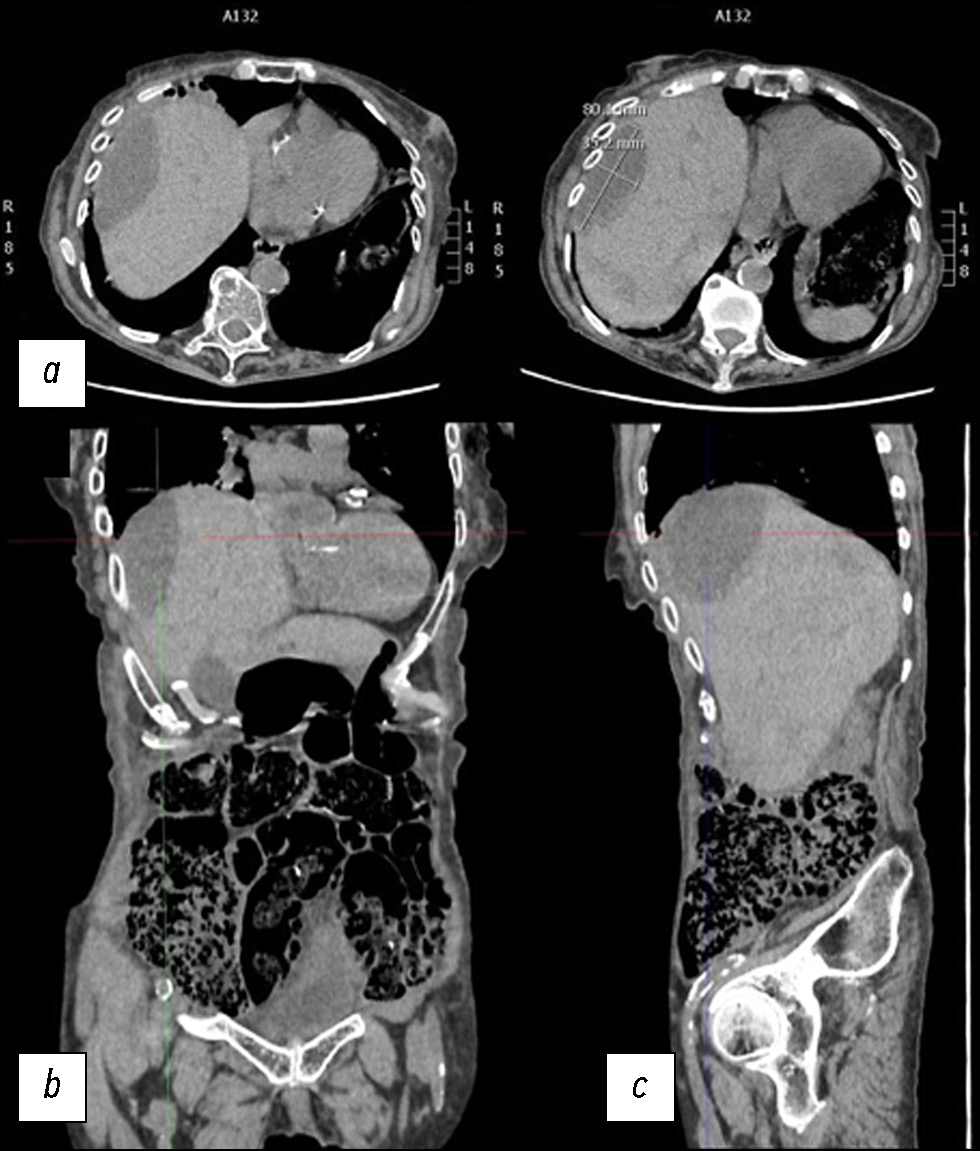

Hepatic parenchymal rupture is a rare but potentially fatal condition that can be caused by trauma, iatrogenic factors, spontaneous causes, etc. This case report describes the diagnostic and therapeutic steps employed in a patient with spontaneous hepatic parenchymal rupture. An older woman came to the emergency department with diffuse stomach pain. After clinical evaluation, she underwent computed tomography. The first computed tomography did not reveal a full-blown parenchymal rupture. Owing to data ambiguity, indicating that the abdominal discomfort could be caused by renal or biliary colic, obtaining an early diagnosis was very difficult. In truth, only few hypodense oval shapes with characteristic suprafluid densitometry were found in the liver parenchyma. However, after a few days, the discomfort persisted, and as the condition worsened, the patient underwent additional radiological examinations, which revealed the rupture of the liver parenchyma that required arteriography, and a long hospital stay until clinical resolution.